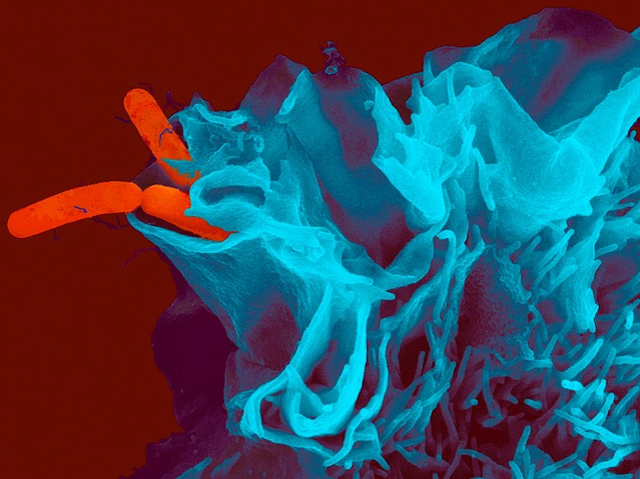

Seagull Sentinels

Risk of human infection by drug-resistant bacteria from seagulls

Antibiotic resistance in bacteria is one of the key medical challenges of this century, and monitoring bacterial populations in the wild demonstrates the scope of the problem. Species in close contact with humans, like gulls, known for scavenging our leftovers at the seaside, are likely to share our bacteria, including antibiotic-resistant strains. Following evidence of antibiotic-resistant Escherichia coli in Australian silver gulls, a recent study on yellow-legged and Audouin’s gulls in the Mediterranean also found resistant strains of Campylobacter jejuni and Salmonella Typhimurium (pictured, in red, invading a human cell). Common causes of diarrhoea, these latter bacteria are transmitted mainly through contaminated food and domestic animals. Finding them in multiple gull species highlights both the potential risk for transmission and the extent of contamination from human and agricultural waste, so gulls could serve as useful sentinel species, providing an indicator of the prevalence of antibiotic resistance in the environment.